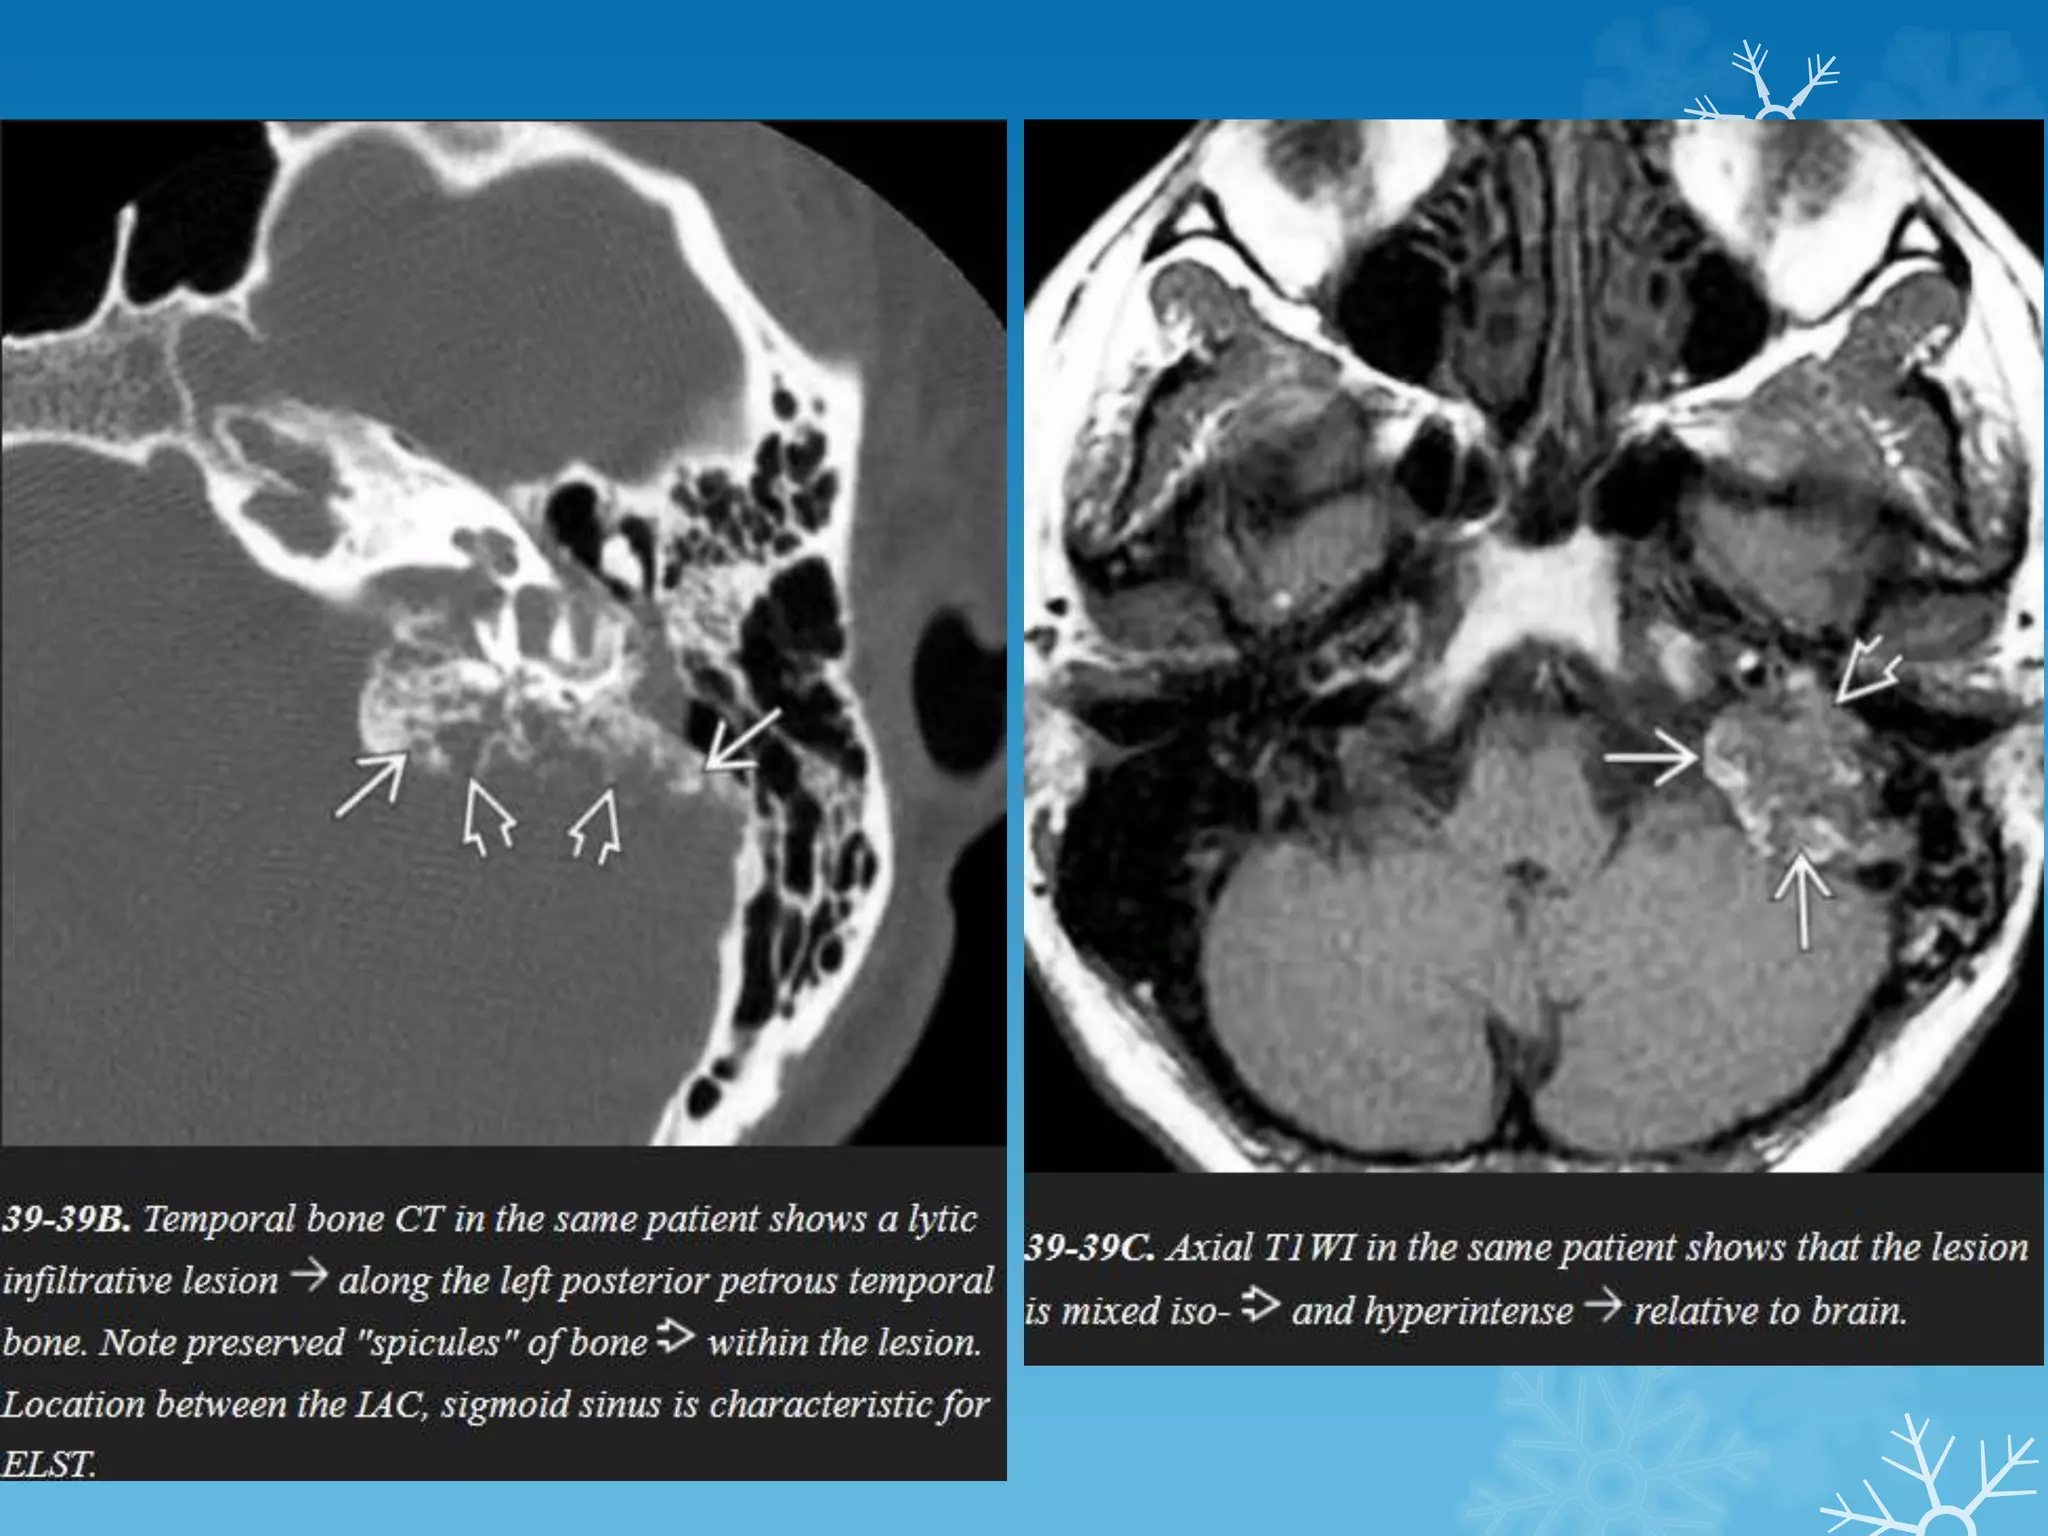

SPOT 5

CT MRI

Endolymphatic sac tumors (ELSTs)